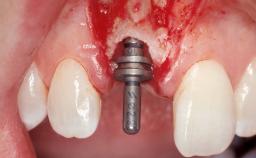

| # of Implants | 1 |

| Type of Implants | One-Piece |

| Attachment | One-Piece |

| Bone Augmentation | Horizontal|Simultaneous |

| Augmentation Materials | Xenogenous|Membrane |

| Soft Tissue Grafting | Simultaneous |